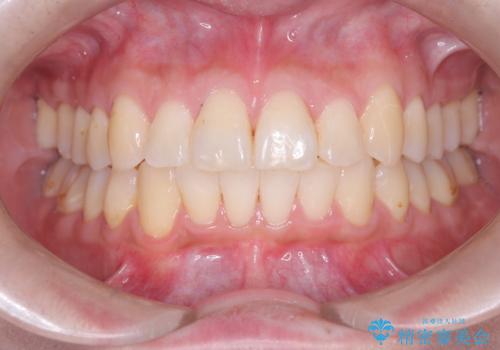

前歯の乱れをスッキリ解消!抜歯矯正で整えた美しい歯並び

担当医 河口智英